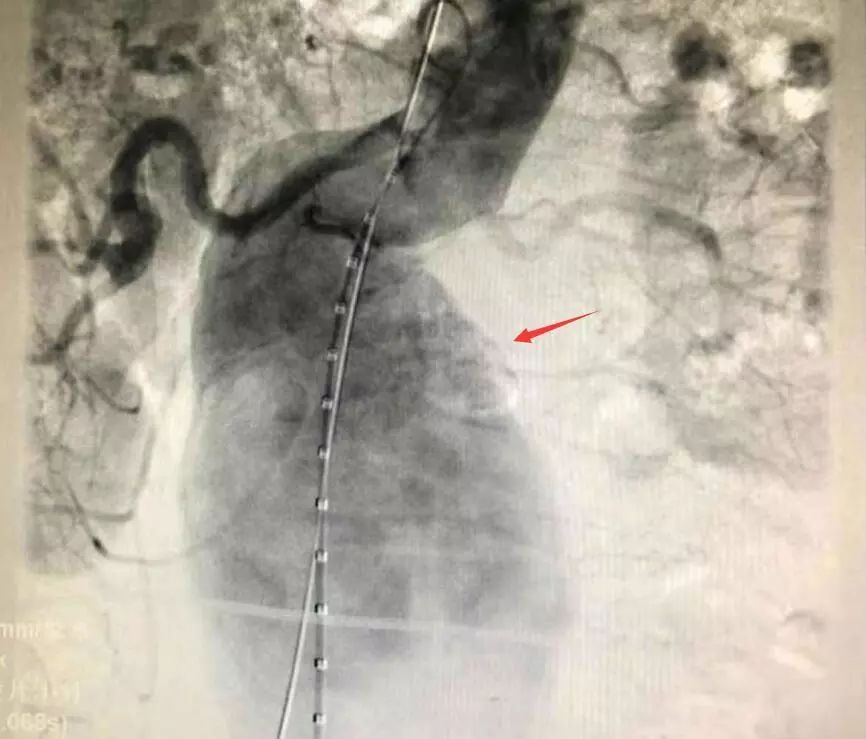

動脈瘤術中顯影

回憶手術過程時,王主任說,老楊的手術相對來說確實難度較高,由于瘤體大,血液在里面形成渦流,導絲前進時容易彎折,無論是支架定位還是支架釋放,整個過程都十分考驗團隊的配合度。常規(guī)手術一般只用到兩個支架,老楊的瘤體較長,用上了四根支架才成功完全隔絕動脈瘤,杜絕內漏的發(fā)生,“就像是在患者的血管內建了一個立交橋,”王主任形容道。